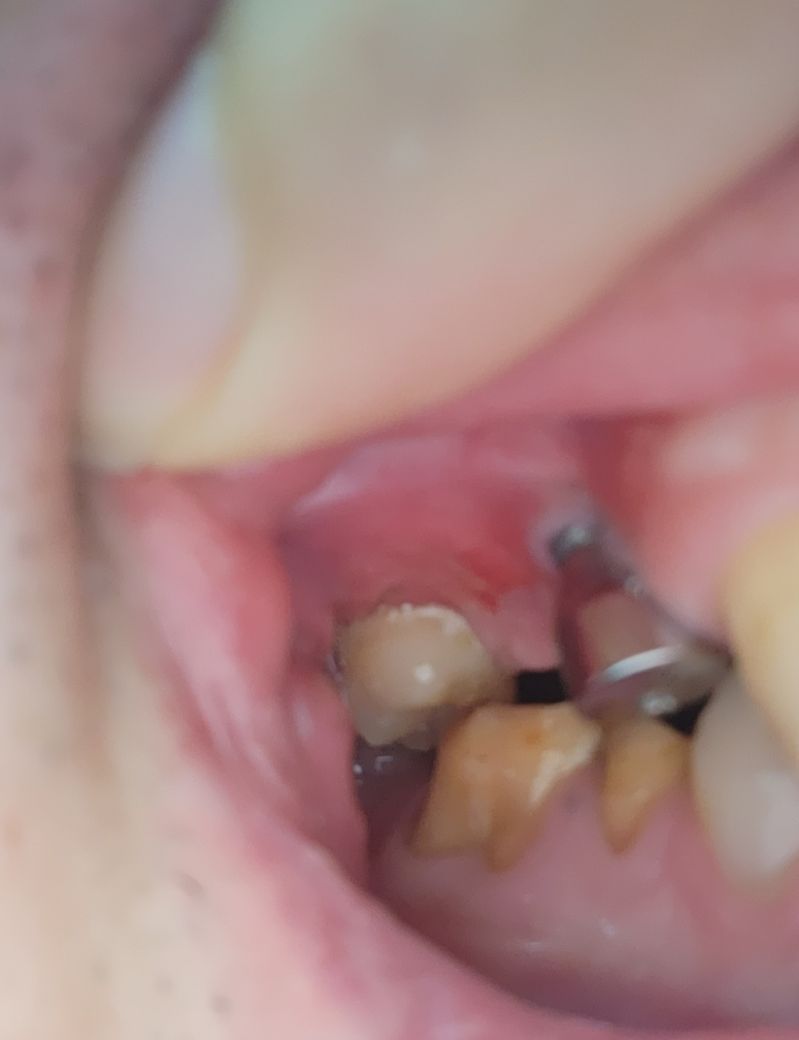

임플란트 염증은 음주나 흡연, 면역력 결핍 등에 의해 생깁니다. 바로 치과를 가보시는게 좋겠습니다.

임플란트식립 부위 잇몸에 염증이 생긴것으로 보입니다. 원인은 치석이 쌓여 잇몸을 자극하였을 가능성도 있으며, 방치시에 잇몸염증이 악화되어 임플란트 식립에도 문제를 주기에 빠른 시일내에 치과 치료가 필요로 됩니다.

임플란트 심으신데 염증이 생겨서 잇몸이 많이 내려간거 같은데 치과에 가셔서 검진을 받아보시는게 좋을것같습니다.